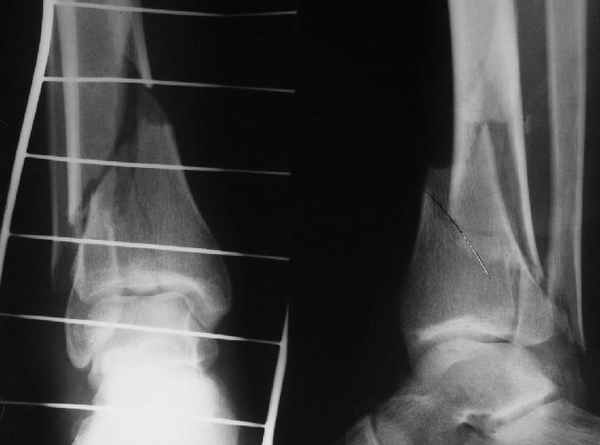

Pilon fracture:

ET> ЕЧ При подобных переломах фиксация малоберцовой кости обеспечивает

ET> низведение латерального тибиального фрагмента - появляется ориентир для

-Появляется ориентир и остов, на чем можно строить восстановление, почему сперва малоберцовую, впервые обьяснили и описали (Pylon type and Ankle fractures) в середине 50х Rienau и Gay.

Восстановливая длину и ротацию малоберцовой кости, затем относительно легче произвести реставрацию остальных элементов перелома дистального эпиметафиза болшеберцовой кости.

конец малоберцевой кости, к нему прикрепляется латеральный суставной фрагмент дистального эпиметафиза большеберцовой кости (как на снимке)

и таранная кость, которые при репозиции малоберцовой кости репонируются автоматически.